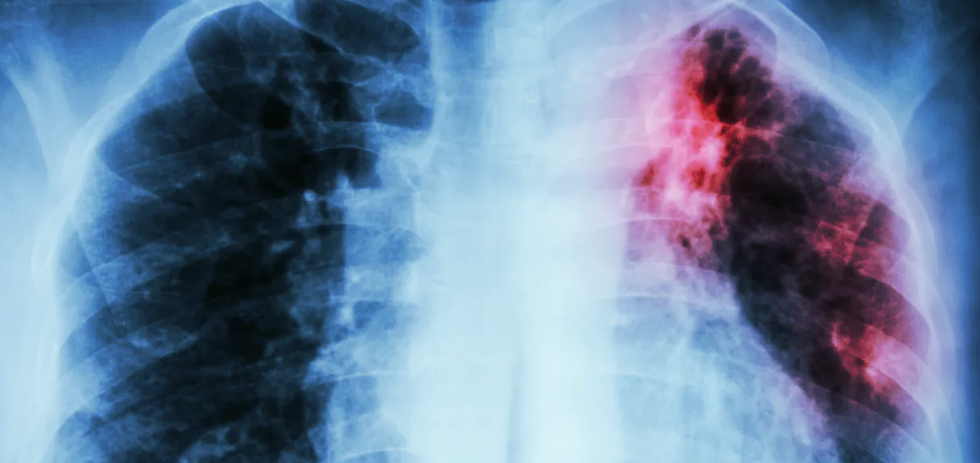

Tuberculosis y covid-19 son enfermedades infecciosas de transmisión aérea. Afectan mayoritariamente al sistema respiratorio y manifiestan una tríada clásica de síntomas: tos, fiebre y disnea. Esto dificulta inicialmente el diagnóstico diferencial, especialmente en países con alta incidencia de tuberculosis.